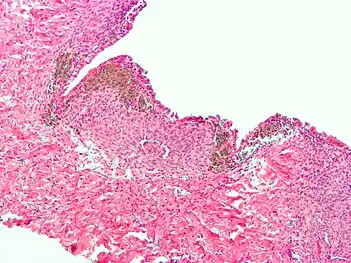

Micrograph of the wall of an endometrioma. All features of endometriosis are present (endometrial glands, endometrial stroma and hemosiderin-laden macrophages).

Histopathology

For a histopathological diagnosis, at least two of the following three criteria should be present:[110]

- Endometrial type stroma

- Endometrial epithelium with glands

- Evidence of chronic hemorrhage, mainly hemosiderin deposits

Immunohistochemistry has been found to be useful in diagnosing endometriosis as stromal cells have a peculiar surface antigen, CD10, thus allowing the pathologist go straight to a staining area and confirm the presence of stromal cells and sometimes glandular tissue is identified that was missed on routine H&E staining.[111]